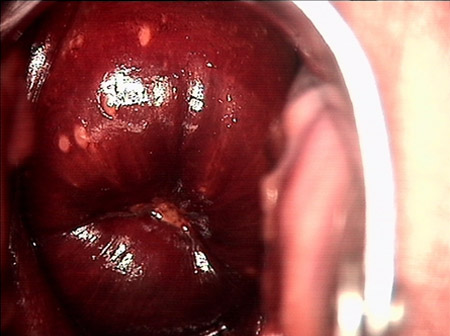

婦科leep錐切手術 CIN2-3

• CIN 2-3CIN 2-3